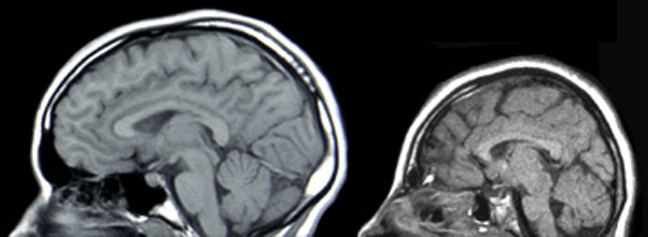

Carrying that Weight

The Atomic Bomb Casualty Commission (ABCC) was created in 1946 under President Truman’s orders to conduct research on the latent effects of radiation among atomic bomb survivors. Alongside the Japanese National Research Council, they found that cancer was the greatest long-term risk from exposure to a nuclear bomb. This is thought to result from the damage that ionizing radiation can cause to DNA structure. For example, high exposure to ionizing radiation may lead to severed double strands, resulting in newly separated and different pieces of DNA. Accumulation of these mutations leads to the development of cancers throughout the body. Among the cancers reported in hibakusha are nervous system cancers, such as Schwannoma, a tumor developed from Schwann cells. These cells are a type of glia, whose role is to support the function of brain cells, typically by myelinating their axons for expedient transmission of neural signals. Data from pregnant survivors showed that cancer could also develop as a result of in utero exposure; exposure to high levels of radiation as an embryo resulted in the birth of babies with microcephaly, a neurological condition by a smaller head size compared to healthy children of the same age and sex.